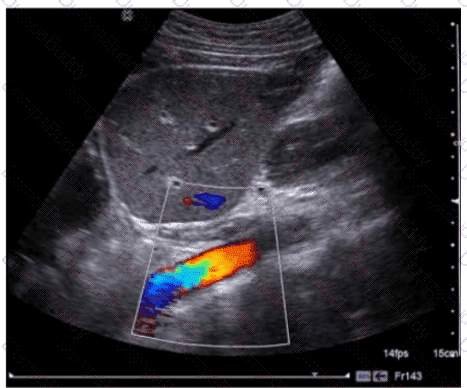

Which adjustment resulted in the change from image A to image B?

SPI Question 22

Options:

A.

Increased transmit frequency

B.

Increased scale

C.

Decreased color gain

D.

Decreased acoustic power